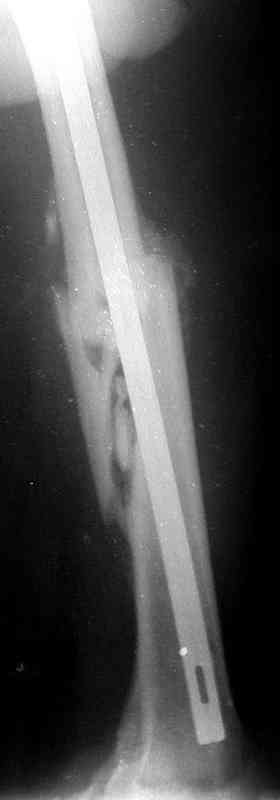

В общем, план тот же - удаление, закрытый реостеосинтез стержнем с блокированием. Лучше с коррекцией не только оси, но и длины. По деталям - может быть много нюансов. Можно удалить стержень, наложить интраоперационный дистрактор, лучше спицевой, растянуть сколько получится, заштифтовать с коррекцией оси с помощью отклоняющих (Poller) спиц/винтов, и в этом "напряжении растяжения" статически запереть. Какие имплантаты доступны?

При таком диаметре штифта не удивительно, что перелом не сросся (кстати, какой диаметр и что за модификация штифта?).

Абсолютно согласен с А.Челноковым, что метод выбора в данной ситуации: удаление штифта, антеградное рассверливание и реостеосинтез массивным штифтом... и не обязательно блокированным... на мой взгляд, можно использовать и общепринятый штифт типа Кюнчера.

Оптимально - титановый блокируемый дистально и проксимально штифт, с анатомической кривизной, диаметром 12-14 мм. Каннюлированный или солидный - непринципиально.

Альтернатива - малоинвазивно длинную LC-LCP.

1) Биомеханически штифт в центре кости выгоднее пластины снаружи

2) Технически штифтование проще

3) Штифтование менее травматично для мягких тканей

4) На штифте рекомендуем полную нагрузку сразу

1) Риск перелома пластины, даже самой фирменной, в условиях замедленного сращения значительно больше, чем штифта

2) Восстановить ось на пластине при малоинвазивной технике совсем непросто

3) Открытая процедура реостеосинтеза бедра пластиной травматична для мягких тканей и для кости.